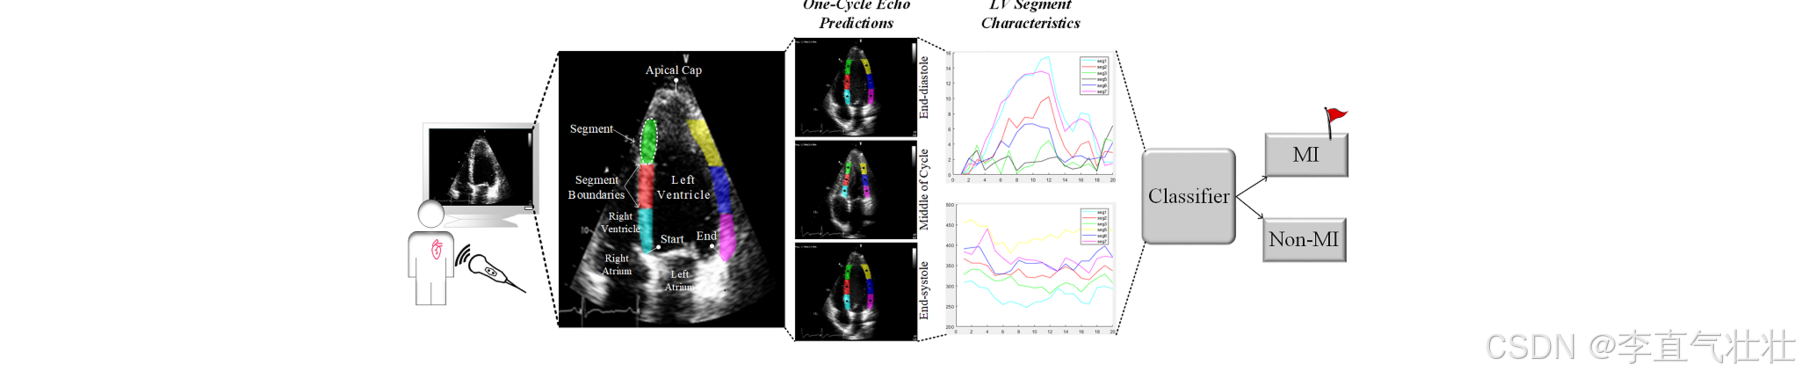

HMC-QU

该数据集包括在 2018 年和 2019 年期间获得的 162 个心尖 4 腔 (A4C) 视图二维超声心动图 (echo) 记录的集合.用于检测心脏左心室 (LV) 壁上的心肌梗塞(心脏病发作). 视频来自一年内执行的 10, 000 多个检查, 其中包括 800 多例因急性 ST 段抬高心肌梗死 (MI) 入院的病例. HMC-QU 数据集中包含的回声属于 93 名 MI 患者(均为首次和急性 MI)和 69 名正常(非 MI)受试者

链接: link